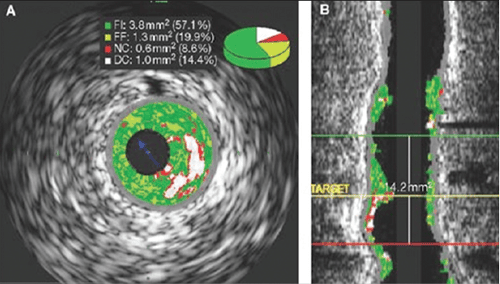

Siêu âm trong lòng mạch là kỹ thuật siêu âm sử dụng ống thông đặc biệt nhằm quan sát, đánh giá hình ảnh cấu trúc mạch máu. Một đầu của ống thông được gắn vào đầu dò phát sóng siêu âm, đầu còn lại được kết nối với hệ thống máy ghi nhận và xử lý hình ảnh. Ống thông sẽ được luồn qua một dây dẫn thẳng vào trong lòng mạch máu, đến vị trí cần khảo sát và ghi lại hình ảnh mạch máu. Thông qua hình ảnh thu được, các bác sĩ sẽ đánh giá tình trạng mạch máu và chẩn đoán các bệnh lý liên quan.

Siêu âm trong lòng mạch là phương pháp chẩn đoán hình ảnh được áp dụng trong các trường hợp nghi ngờ có bệnh lý về mạch máu, nhất là bệnh lý về động mạch vành. Kết quả thu được từ siêu âm trong lòng mạch phản ánh chi tiết, cụ thể tình trạng mạch máu, bao gồm: kích thước, hình dạng, các tổn thương xơ vữa mạch, vôi hóa, huyết khối… Do đó trong các trường hợp khó xác định bệnh động mạch vành thì ngoài việc chụp mạch vành thông thường, bác sĩ thường chỉ định siêu âm trong lòng mạch kết hợp để có kết quả chẩn đoán chính xác.

Thông qua siêu âm trong lòng mạch, bác sĩ có thể đưa ra phương hướng xử lý phù hợp như: vị trí đặt stent, kích thước stent, các dụng cụ cần thiết cho quá trình can thiệp…

Sau khi kết thúc điều trị, siêu âm trong lòng mạch cũng được chỉ định để đánh giá hiệu quả điều trị, khảo sát nguyên nhân tái hẹp trong các trường hợp tái hẹp sau khi can thiệp stent.

Ống thông IVUS là một ống mỏng. Một đầu của ống gắn vào đầu dò siêu âm, đầu còn lại kết nối với máy tính để truyền tín hiệu từ đầu dò thành hình ảnh trên màn hình. Siêu âm trong lòng mạch giống các kỹ thuật siêu âm khác, cũng sử dụng sóng âm thanh tần số cao để ghi lại hình ảnh cấu trúc mạch máu.

Tùy từng tình trạng cụ thể mà một số bệnh nhân có thể sẽ được chỉ định gây mê toàn thân, còn lại bệnh nhân sẽ được gây tê tại chỗ. Bác sĩ sẽ sát khuẩn vị trí đặt ống thông và phủ vải phẫu thuật lên trên. Một dụng cụ dẫn đường sẽ được bác sĩ luồn vào động mạch cẳng tay hoặc động mạch đùi. Ống thông được luồn vào dụng cụ dẫn đường, đi đến vị trí cần khảo sát trên một sợi dây dẫn mềm. Quá trình này được thực hiện dưới hướng dẫn của màn tăng sáng. Tại đây, sóng siêu âm sẽ tạo ra hình ảnh của cấu trúc mạch máu, phản xạ lại màn hình hiển thị.